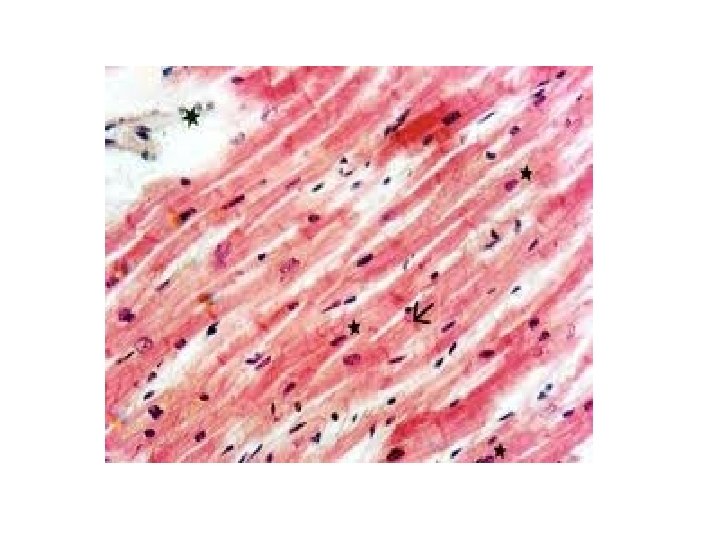

Tejido muscular • Formado por miocitos o fibras musculares.

• Tejido muscular –Tejido muscular liso –Tejido muscular estriado o esquelético –Tejido muscular cardíaco

Tejido muscular